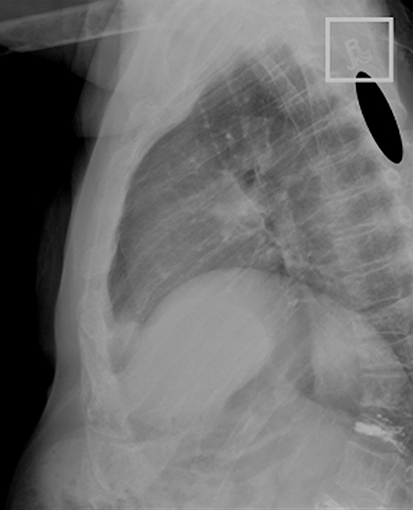

Some flat panel systems can take images faster than the detector can accommodate. If an image is taken prior to the detector releasing all of the signal from the previous image, a faint image of the previous exposure may be visible. This is known as image lag. Image lag is almost a double exposure of sorts. When the detector is unable to get rid of all of the signal from the previous image, lag can occur. Rapid succession of images is only one reason for image lag. Another reason image lag might occur is overexposure or an area with little beam attenuation, such as a technologist’s lead marker location. In Fig. 5.9, a faint R is visible in the proximal thoracic spinous processes. The R is left over from the previous image. The following techniques can be used to reduce the possibility of image lag: